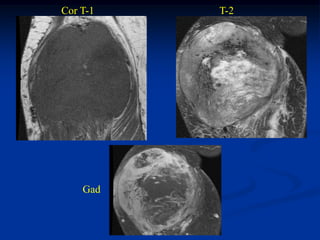

Case #253.2               Desmoid tumor

56 yr male with tender soft tissue mass volar aspect of wrist 6 mos

Cor T-1         T-2

Gad

Axial T-1   T-2